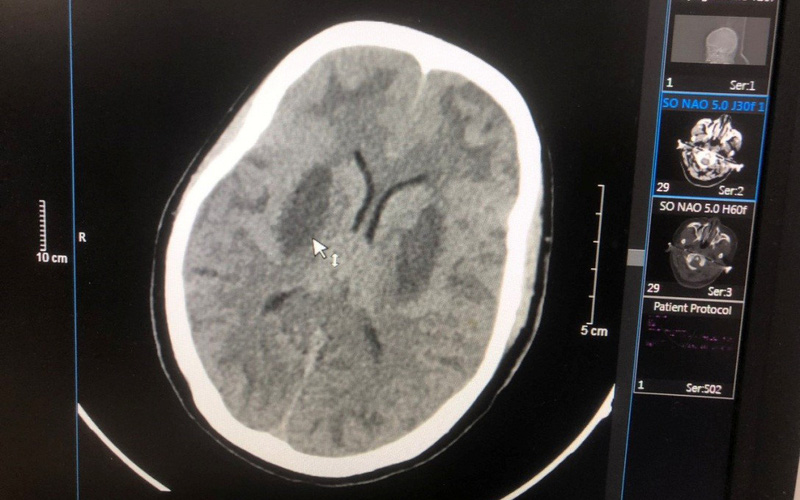

Bệnh nhân bắt đầu bị bệnh từ ngày 27/2 với triệu chứng mờ mắt, đau đầu, buồn nôn, sau đó lơ mơ dần. Bệnh nhân được đưa đến Bệnh viện Thuận Thành, sau đó được chuyển đến Bệnh viện Bạch Mai. Ngày 28/2, bệnh nhân nhập Trung tâm Chống độc trong tình trạng hôn mê, tụt huyết áp, nhiễm toan chuyển hóa nặng, nồng độ methanol trong máu là 123,16 mg/dL, não tổn thương nặng hai bên. Dù đã được các bác sĩ khẩn trương cấp cứu, hồi sức, giải độc, lọc máu, tuy nhiên não tổn thương nặng không hồi phục nên gia đình đã xin về và bệnh nhân đã qua đời.

Sau đó, bệnh nhân được chuyển tới Trung tâm Chống độc Bạch Mai trong tình trạng hôn mê, tụt huyết áp, nhiễm toan chuyển hóa nặng, tổn thương não nặng hai bên, nồng độ methanol trong máu là 125 mg/dL, không có ethanol. Bệnh nhân đã được cấp cứu điều trị hồi sức giải độc lọc máu, hiện tri giác có cải thiện nhưng não vẫn tổn thương và phù não nhiều, tổn thương mắt.